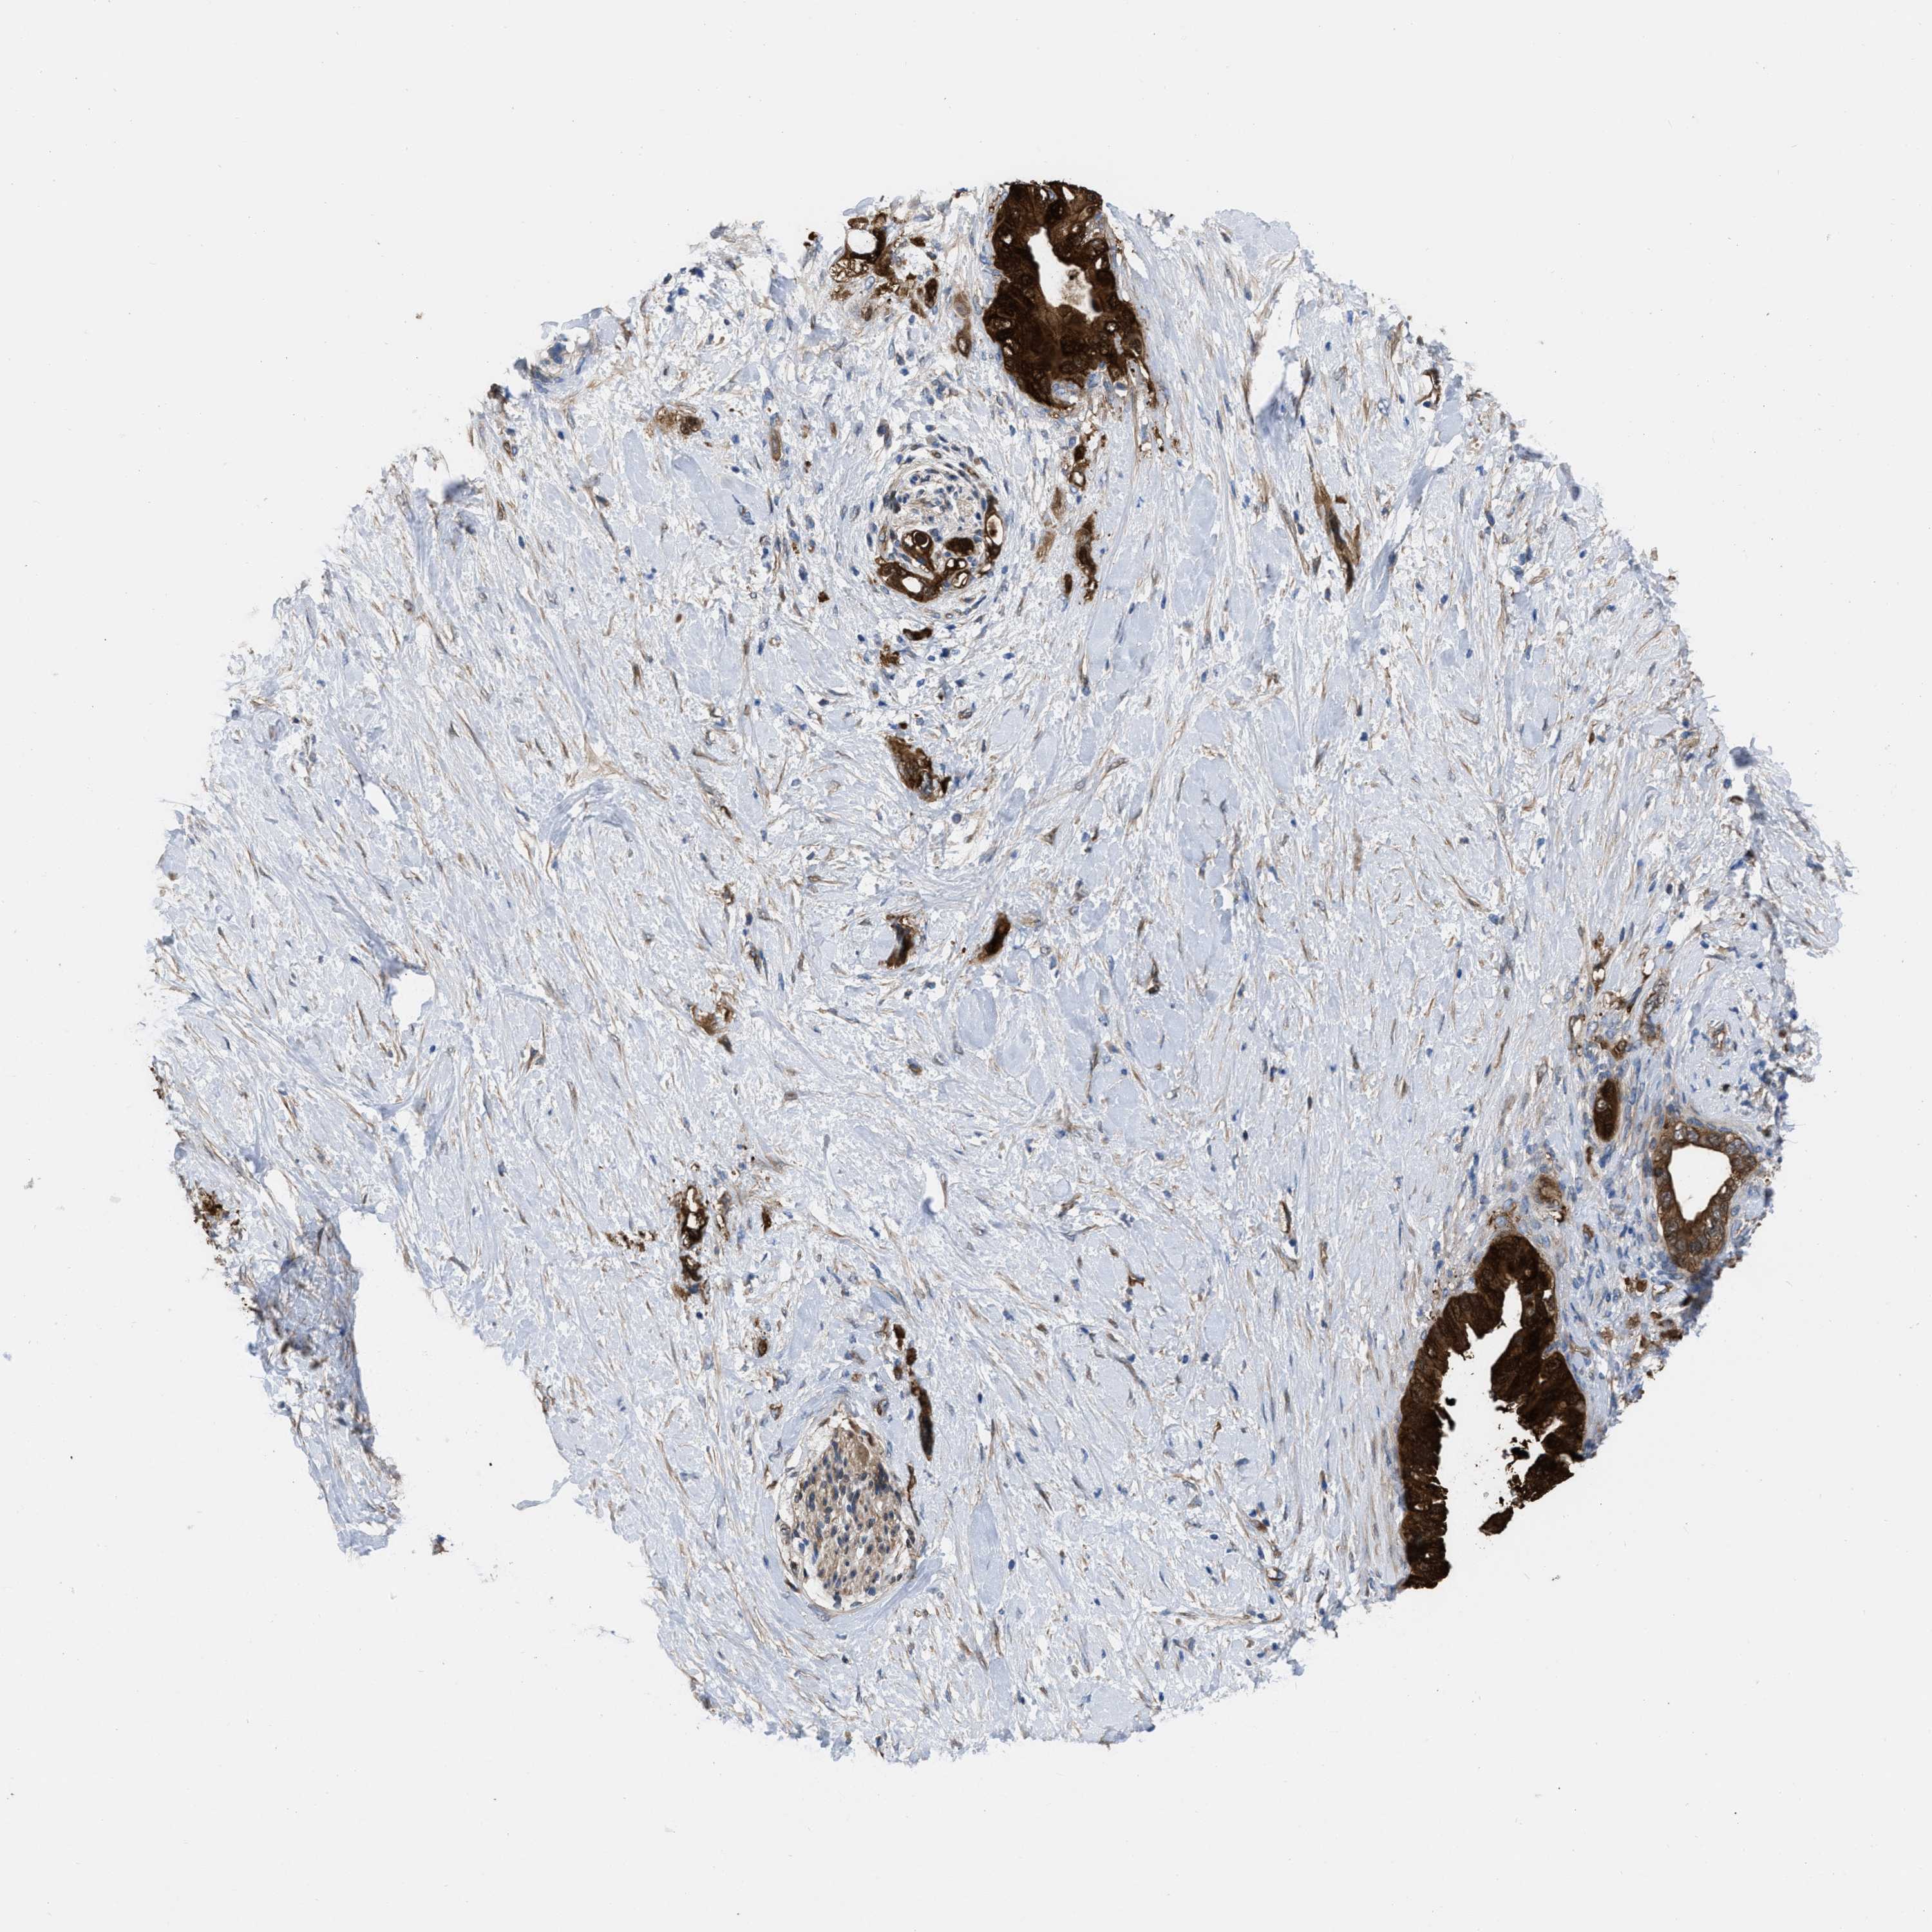

PANCREATIC CANCER - Protein expressioni

A mouse-over function shows sample information and annotation data. Click on an image to view it in a full screen mode. Samples can be filtered based on level of antibody staining by selecting one or several of the following categories: high, medium, low and not detected. The assay and annotation is described here.

Note that samples used for immunohistochemistry by the Human Protein Atlas do not correspond to samples in the TCGA dataset.

Antibody stainingi

Antibody staining in the annotated cell types in the current human tissue is reported as not detected, low, medium, or high, based on conventional immunohistochemistry profiling in selected tissues. This score is based on the combination of the staining intensity and fraction of stained cells.

Each image is clickable and will lead to virtual microscopy that enables deeper exploration of all samples and also displays staining intensity scores, fraction scores and subcellular localization as well as patient and tissue information for each sample.

Antibody HPA003747

Antibody HPA019769

Staining

High

Medium

Low

Not detected

Intensity

Strong

Moderate

Weak

Negative

Quantity

>75%

75%-25%

<25%

None

Location

Nuclear

Cytoplasmic/membranous

Cytoplasmic/membranous,nuclear

Adenocarcinoma, NOS

Adenocarcinoma, metastatic, NOS